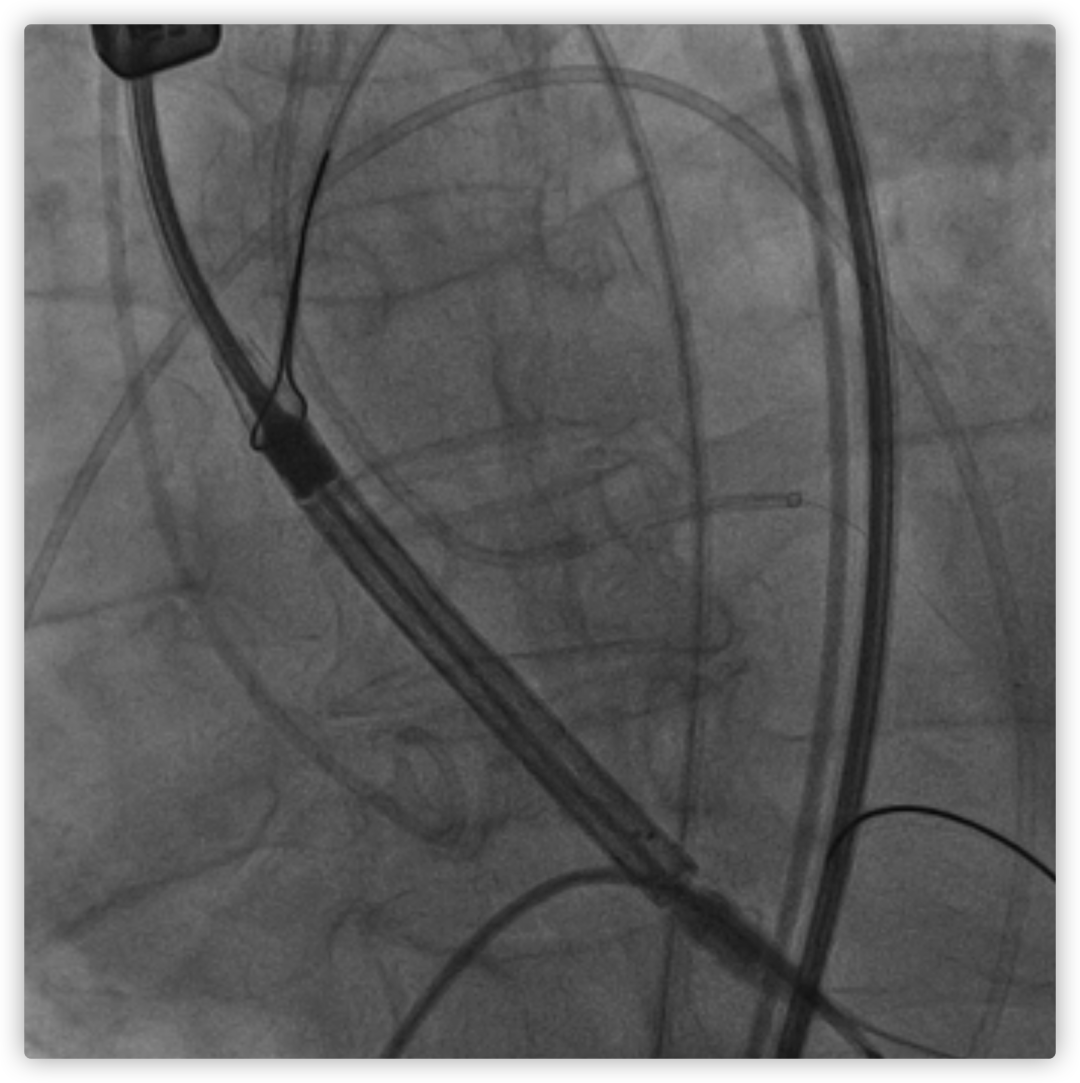

26VenusAplus+snare

瓣膜内22mm球囊后扩张,左冠无显影

LM烟囱支架植入4.0*30mm